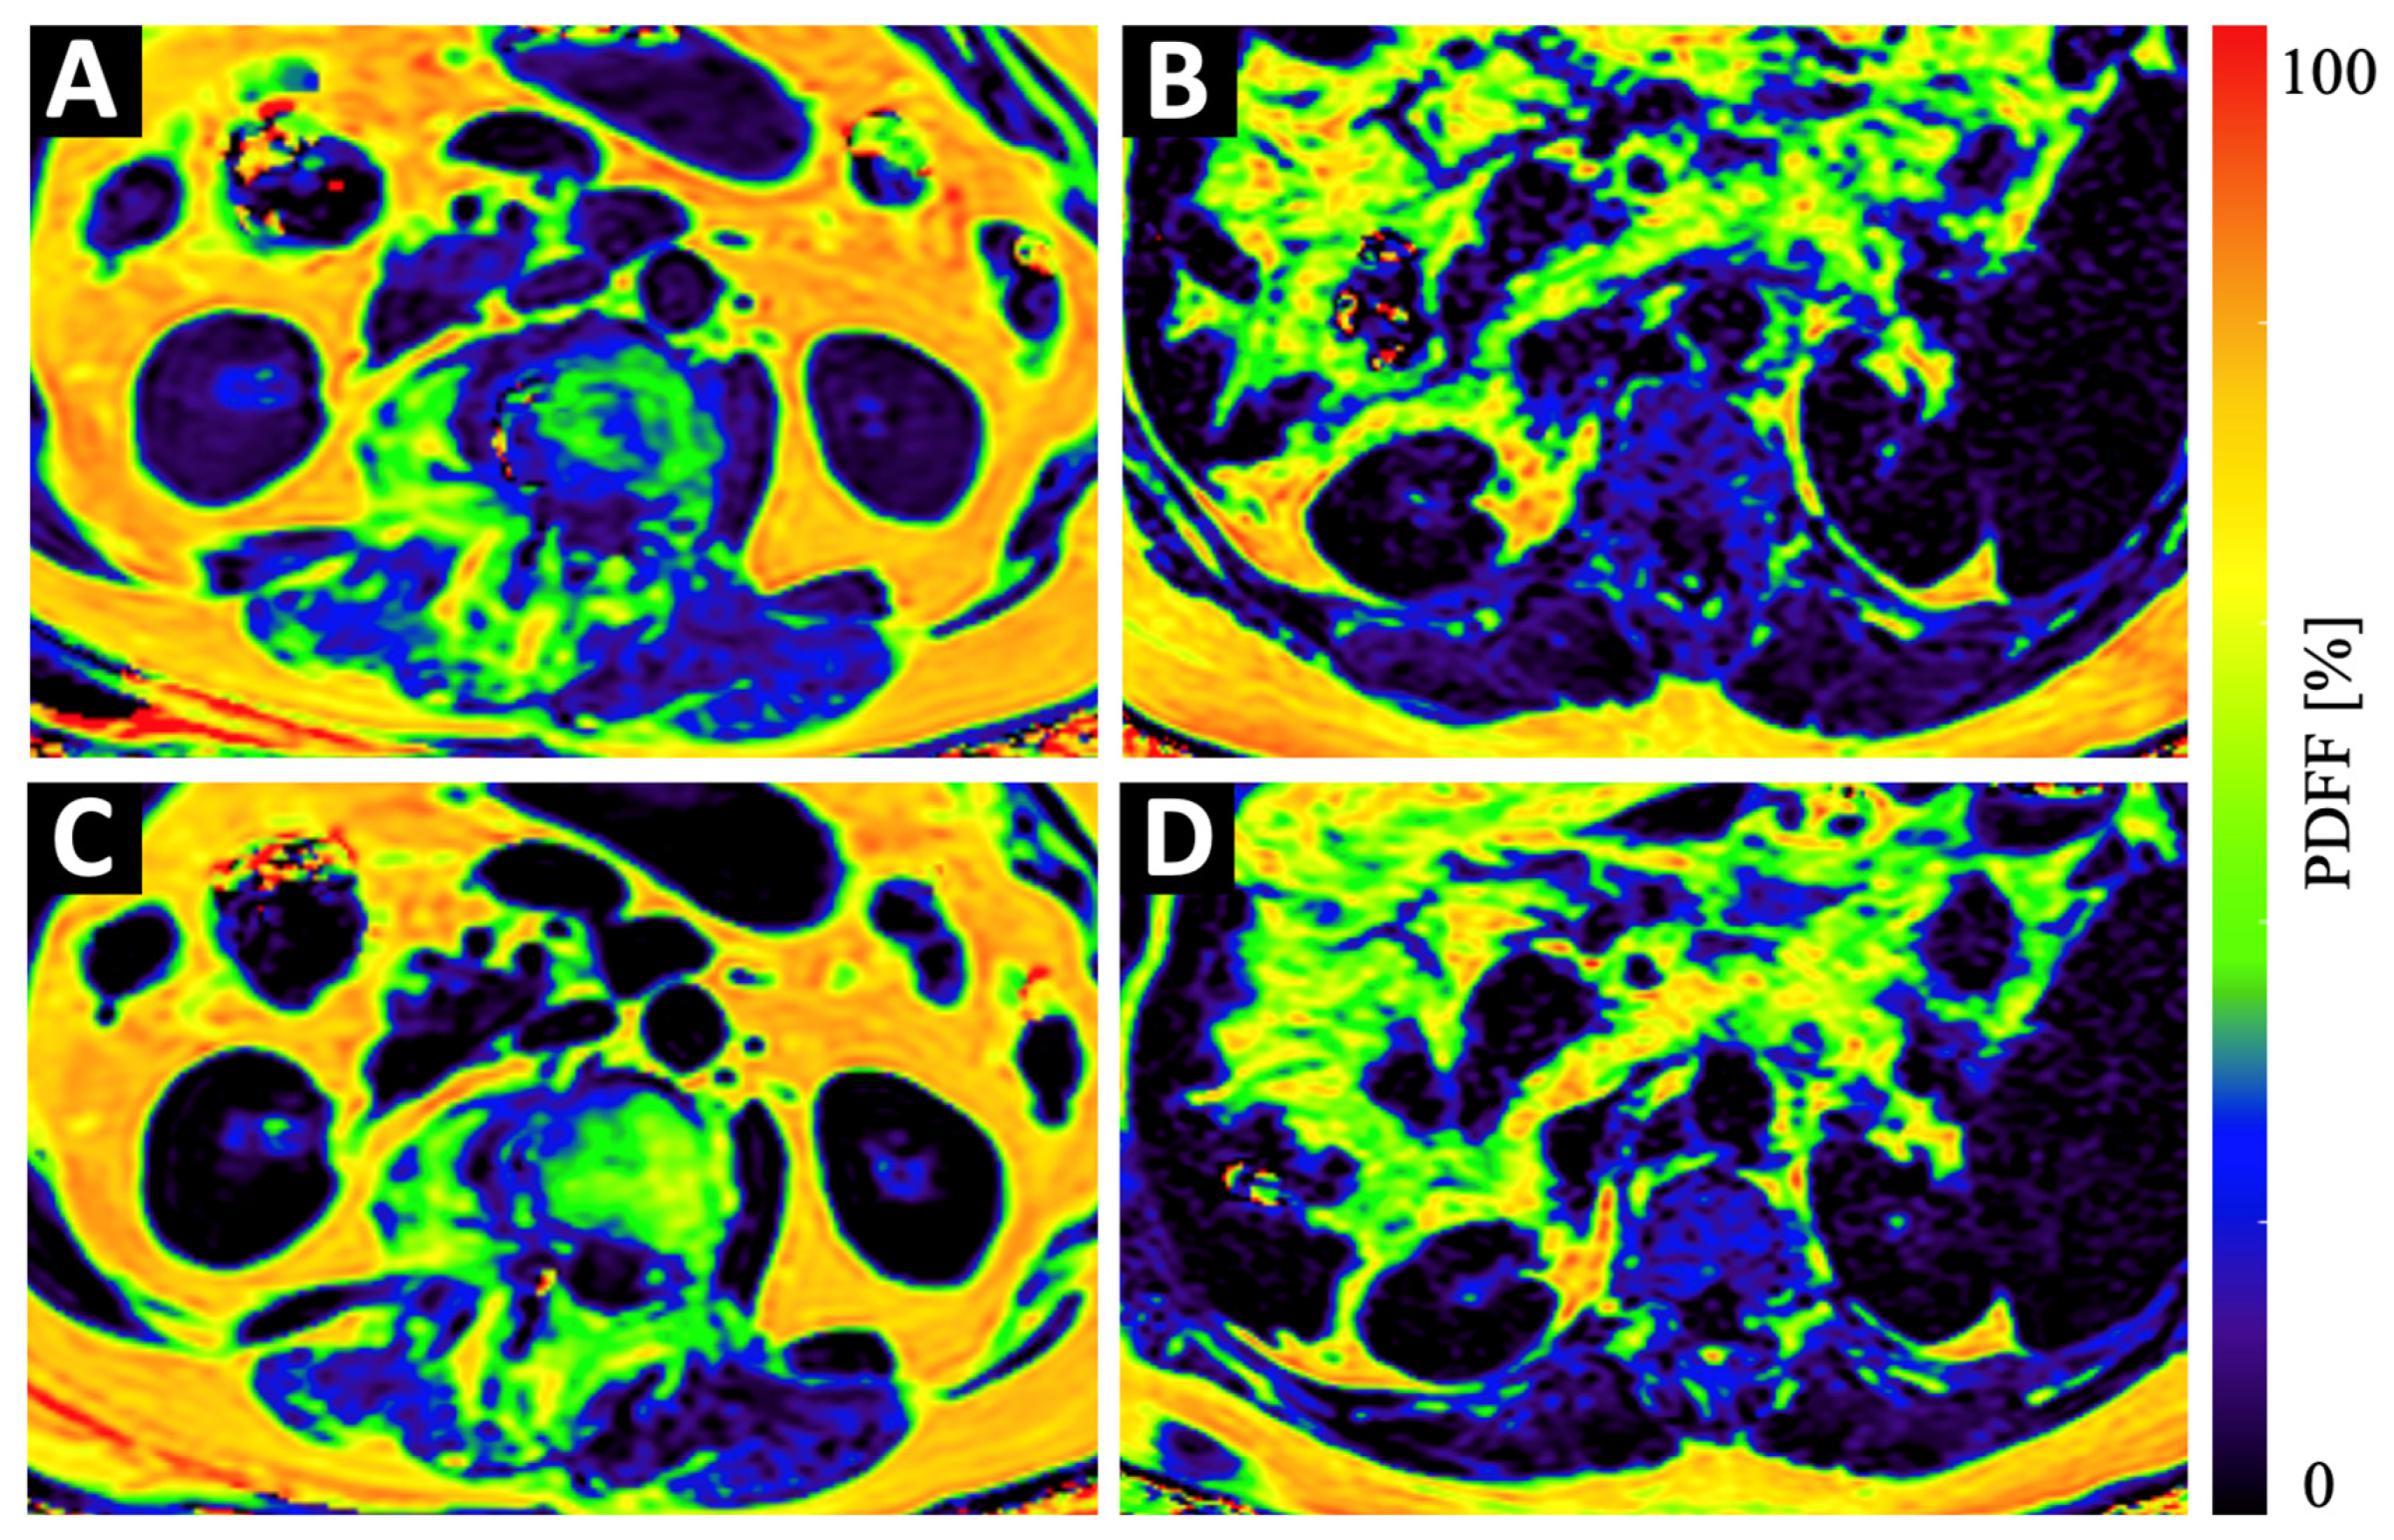

2.3. Magnetic Resonance Imaging Measurements

2.4. Paraspinal Muscle and Vertebra Segmentation

- Sollmann, N.; Dieckmeyer, M.; Schlaeger, S.; Rohrmeier, A.; Syvaeri, J.; Diefenbach, M.N.; Weidlich, D.; Ruschke, S.; Klupp, E.; Franz, D.; et al. Associations Between Lumbar Vertebral Bone Marrow and Paraspinal Muscle Fat Compositions-An Investigation by Chemical Shift Encoding-Based Water-Fat MRI. Front. Endocrinol. 2018, 9, 563. [Google Scholar] [CrossRef]